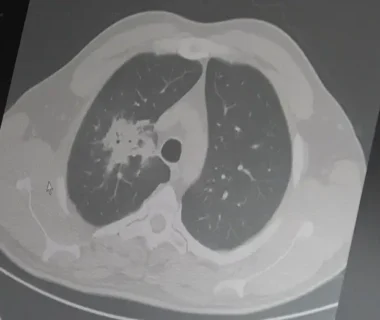

Her yıl 10 milyondan fazla kişinin yakalandığı dünyanın en ölümcül hastalıklardan biri olan tüberküloz nedeniyle 2024’te 1 milyondan fazla kişi hayatını kaybetti. Alman bilim insanı Robert Koch’un verem mikrobunu ortaya çıkardığı günün anısına 24 Mart “Dünya Tüberküloz Günü” olarak kabul ediliyor. […]